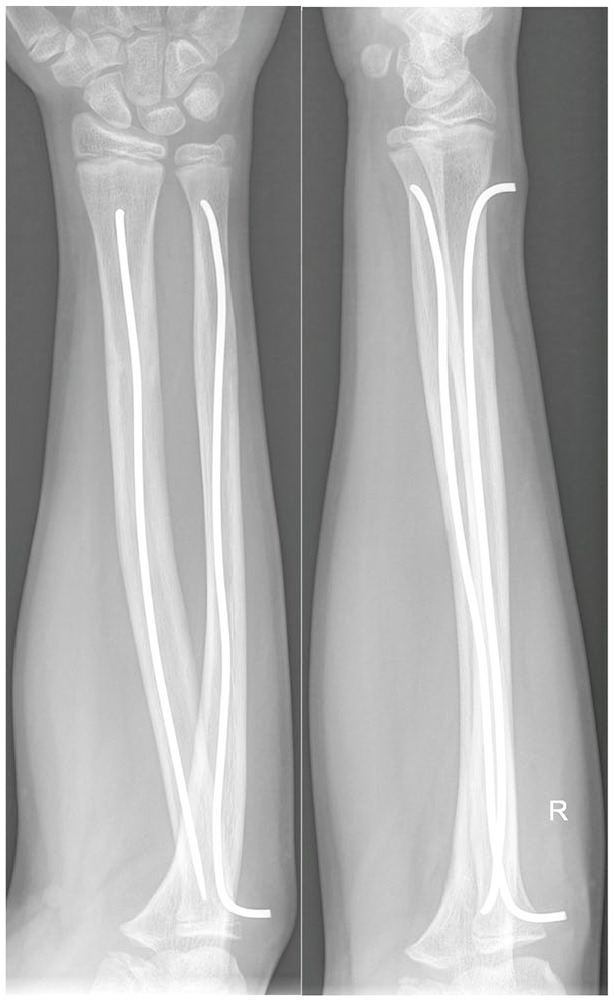

Methods: A 4-year prospective study of healthy children with shaft fractures of the forearm bones (treated with minimally invasive osteosynthesis) or femur (treated by traction or by minimally invasive osteosynthesis). All children had their vitamin D levels examined four times-at the time of the injury, 1, 3, and 5 months after the injury. Also, all children underwent radiograph follow-ups (same time as blood tests) to evaluate fracture healing. Children were, in the beginning, blindly divided into two similarly sized groups-one group was orally administered cholecalciferol throughout the follow-up, the second group was not, and we compared those groups.

Results: Altogether, 63 children were included in the study-36 supplemented and 27 non-supplemented. In supplemented children, the vitamin D levels increased statistically significantly during the follow-up period, in contrast to the non-supplemented group. The fracture healing on radiographs was also statistically significantly faster and better in the supplemented group. When we divided children according to fracture type, we observed statistically significantly better fracture healing in children with forearm fractures in the supplemented group for the whole study period. In children with femoral fractures, the healing in the supplemented group was statistically significantly better after 3 months; however, after 1 and 5 months, the difference was not statistically significant.